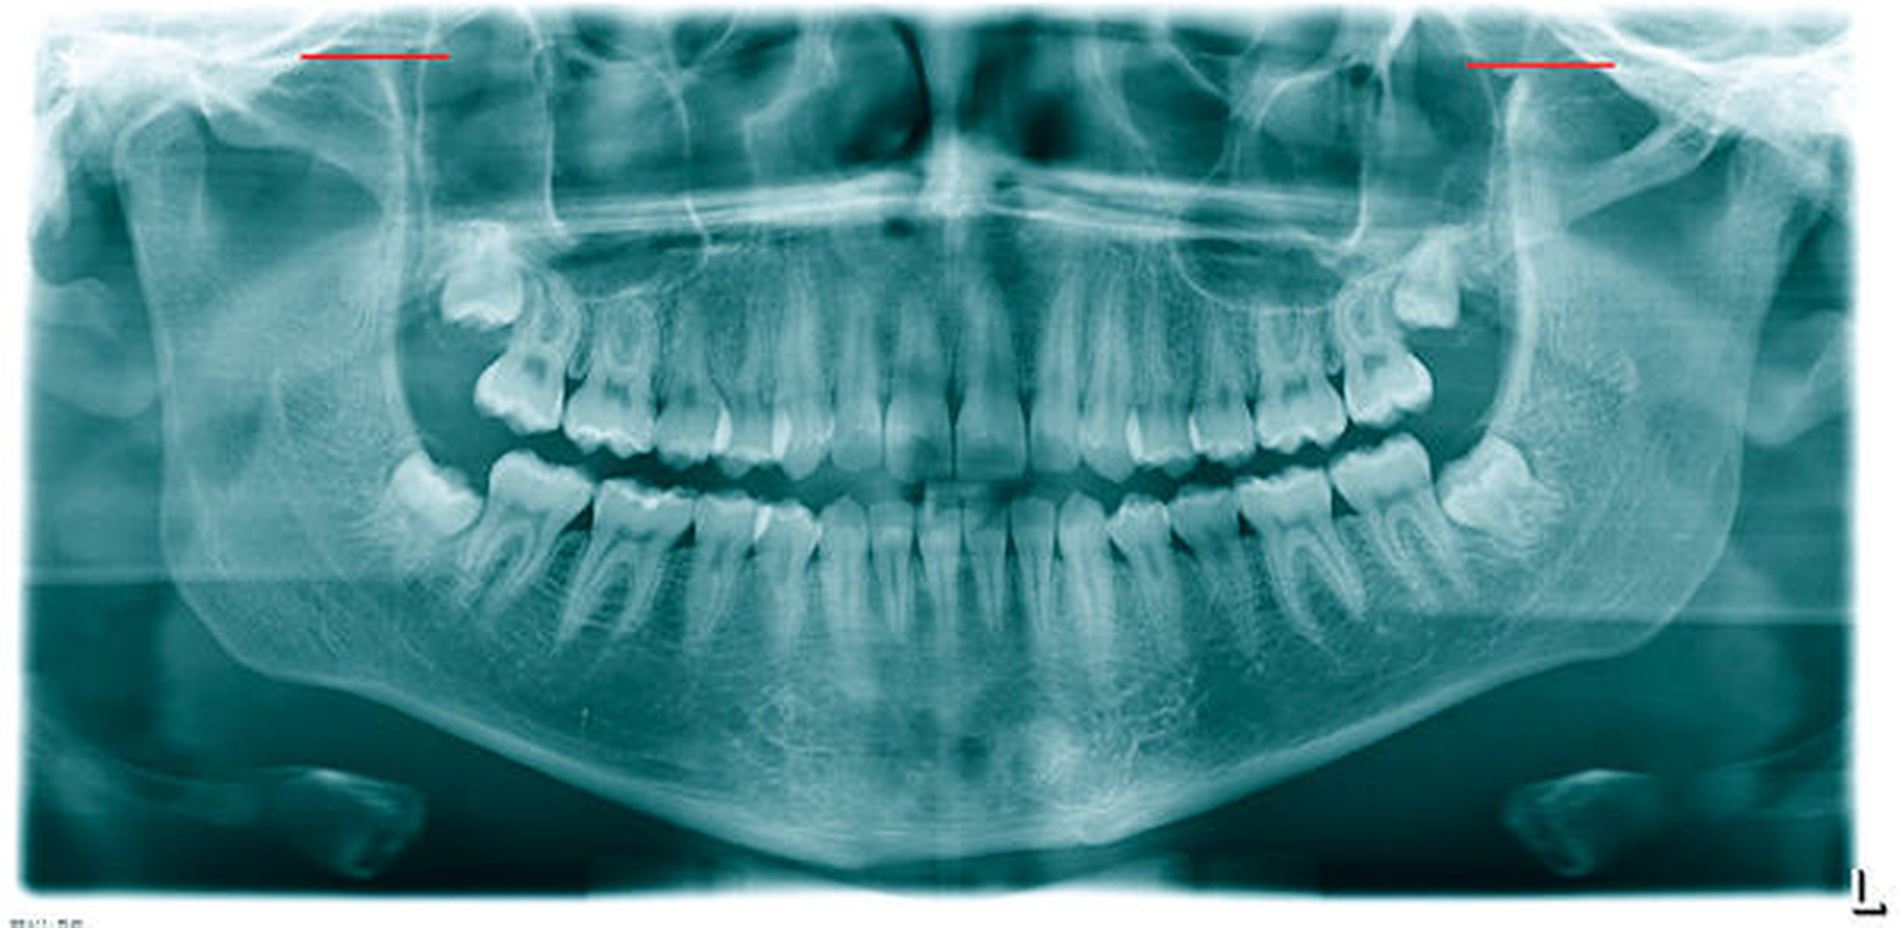

Der Patient erhielt daraufhin als konventionelle Röntgendiagnostik ein Orthopantomogramm (OPG). Hier bestätigte sich die Verdachtsdiagnose einer ausgeprägten, beidseitigen Elongation des Proc. coronoideus (Abbildung 2). Nebenbefundlich zeigten sich die vier Weisheitszähne retiniert.